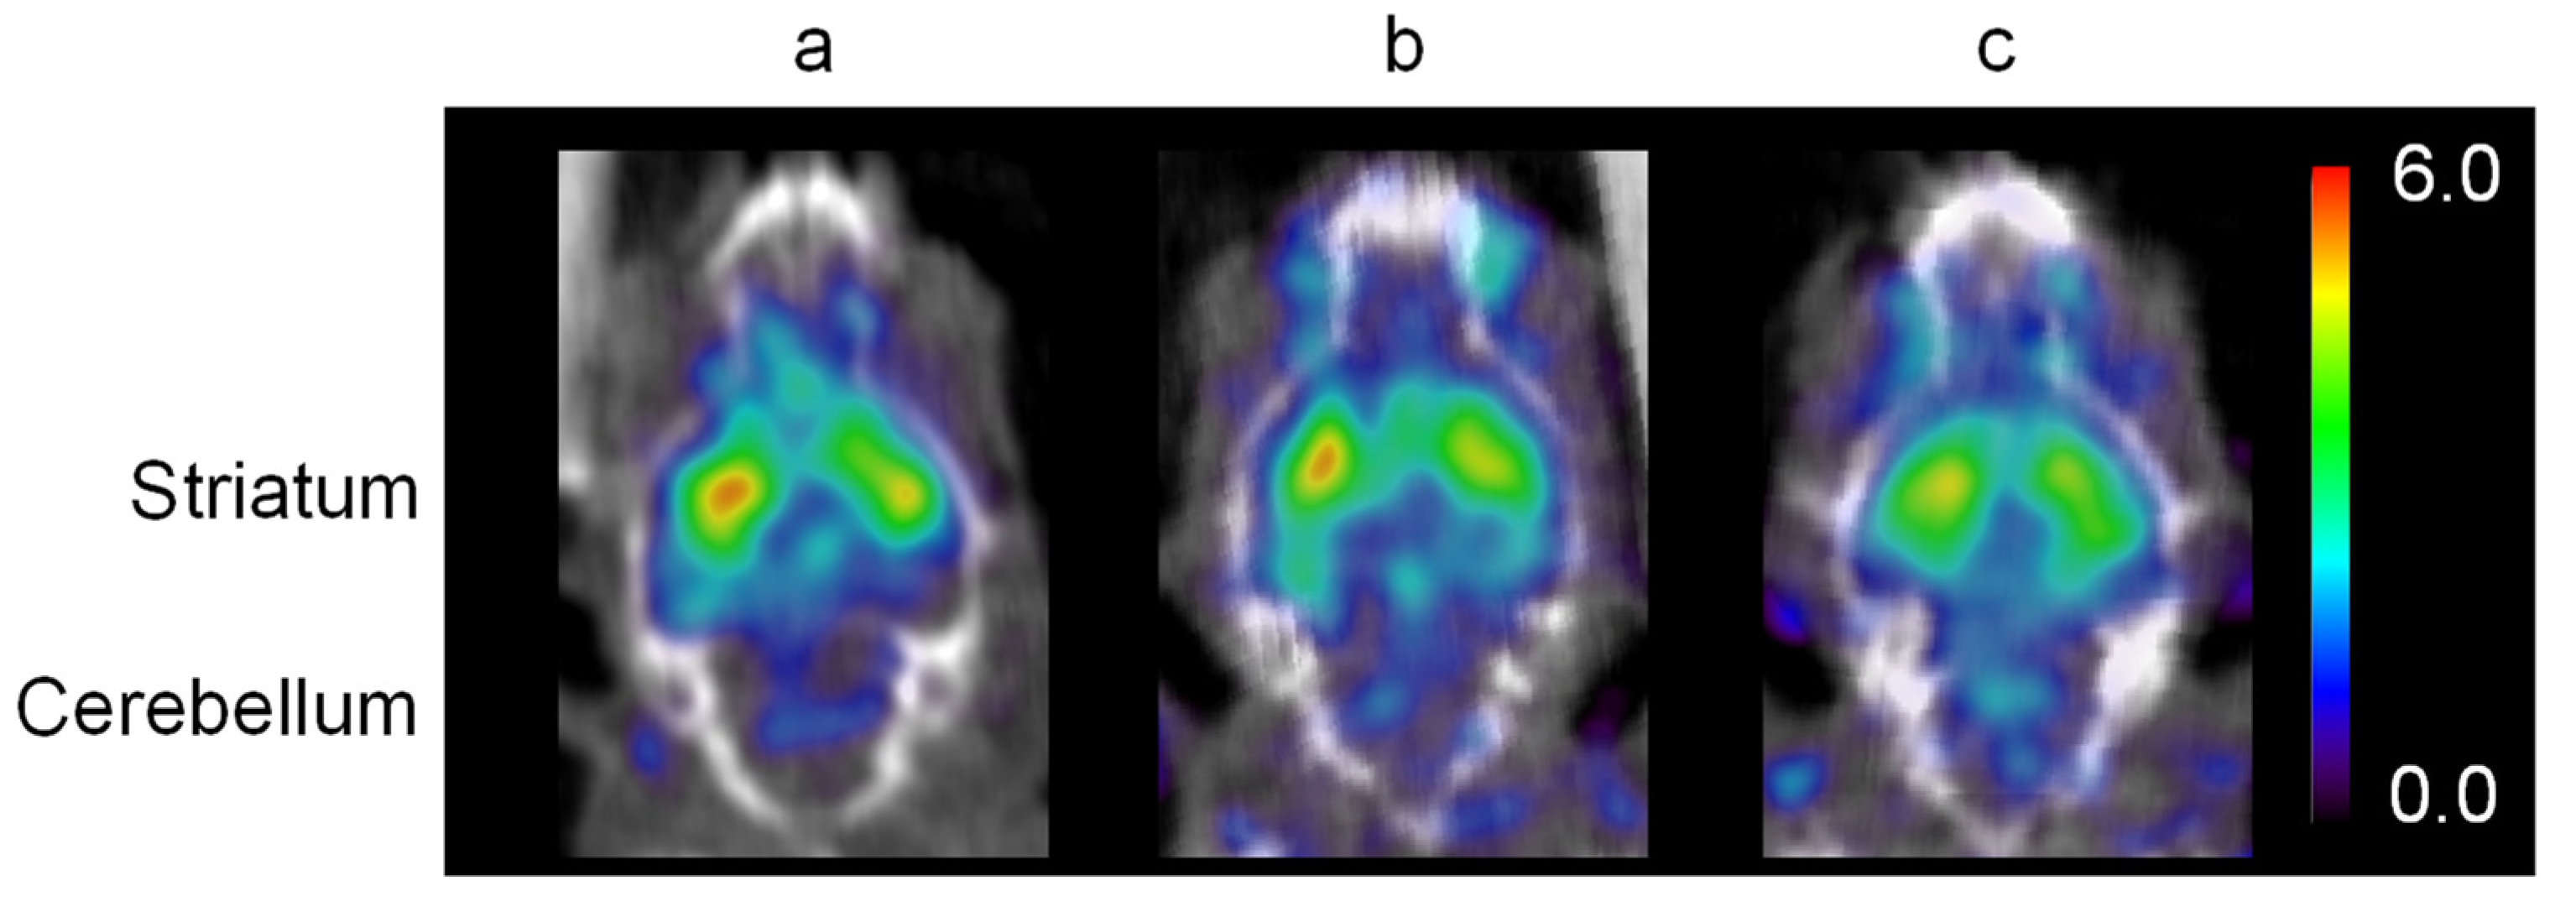

| BP | %RO | |

|---|---|---|

| Control | 1.27 ± 0.16 | |

| IV group | 1.08 ± 0.11 | −4.38 ± 10.95 |

| IN group | 0.67 ± 0.08 * | 35.63 ± 7.35 * |